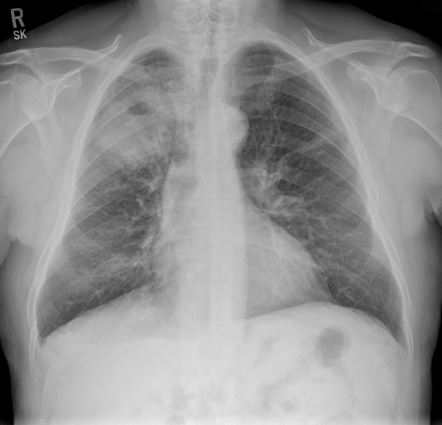

Lung Cancer Screening X Ray

Experience the clarity of Lung Cancer Screening X Ray with our curated collection of comprehensive galleries of images. featuring understated examples of photography, images, and pictures. designed to emphasize clarity and focus. Discover high-resolution Lung Cancer Screening X Ray images optimized for various applications. Suitable for various applications including web design, social media, personal projects, and digital content creation All Lung Cancer Screening X Ray images are available in high resolution with professional-grade quality, optimized for both digital and print applications, and include comprehensive metadata for easy organization and usage. Our Lung Cancer Screening X Ray gallery offers diverse visual resources to bring your ideas to life. Comprehensive tagging systems facilitate quick discovery of relevant Lung Cancer Screening X Ray content. Multiple resolution options ensure optimal performance across different platforms and applications. Time-saving browsing features help users locate ideal Lung Cancer Screening X Ray images quickly. The Lung Cancer Screening X Ray archive serves professionals, educators, and creatives across diverse industries. Instant download capabilities enable immediate access to chosen Lung Cancer Screening X Ray images. Whether for commercial projects or personal use, our Lung Cancer Screening X Ray collection delivers consistent excellence. Professional licensing options accommodate both commercial and educational usage requirements.